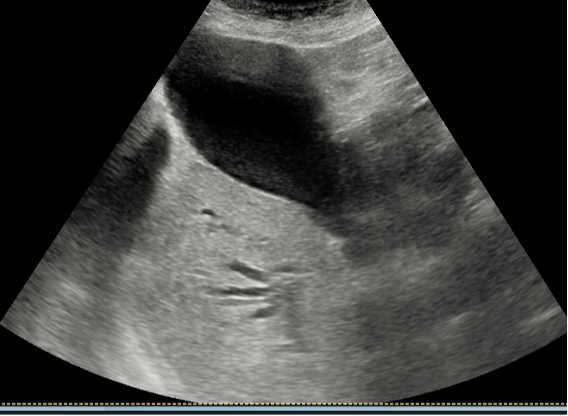

Hallazgos ecográficos